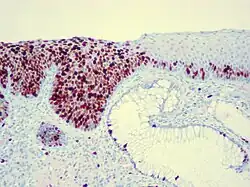

Als Carcinoma in situ (CIS) (wörtlich: „Krebs am Ursprungsort“) wird ein Frühstadium eines epithelialen Tumors ohne invasives Tumorwachstum bezeichnet, welcher ausschließlich intraepithelial wächst, zum Beispiel in der obersten Haut- oder Schleimhautschicht oder in den Milchgängen der Brustdrüse. Die einzelnen Zellen sind dabei mikroskopisch (histologisch, immunhistologisch) in ihren zellulären Strukturen und ihrer Beziehung zueinander von denen eines invasiv wachsenden Karzinoms nicht zu unterscheiden, die Basallamina ist jedoch noch nicht durchbrochen, es liegt keine Tumorinvasion vor. Das Carcinoma in situ metastasiert nicht, d. h., es kann keine Absiedelungen in Lymphknoten oder in anderen Organen bilden.

Das histologische Bild korreliert mit chromosomalen und genetischen Veränderungen. Beim oralen Plattenepithelkarzinom entwickelt sich beispielsweise zuerst ein normales Epithel zum hyperplastischen Epithel durch die Inaktivierung des p16-Gens; die Weiterentwicklung zum dysplastischen Epithel geschieht durch die Mutation des Tumorsuppressorgens p53; das Carcinoma in situ ist gekennzeichnet durch die Amplifikation des Cyclin-D1-Gens; beim invasiven Karzinom lässt sich zudem die Inaktivierung des PTEN-Gens nachweisen. Für eine Vielzahl von Tumoren ist der Verlust von solchen Tumorsuppressorgenen beschrieben worden.